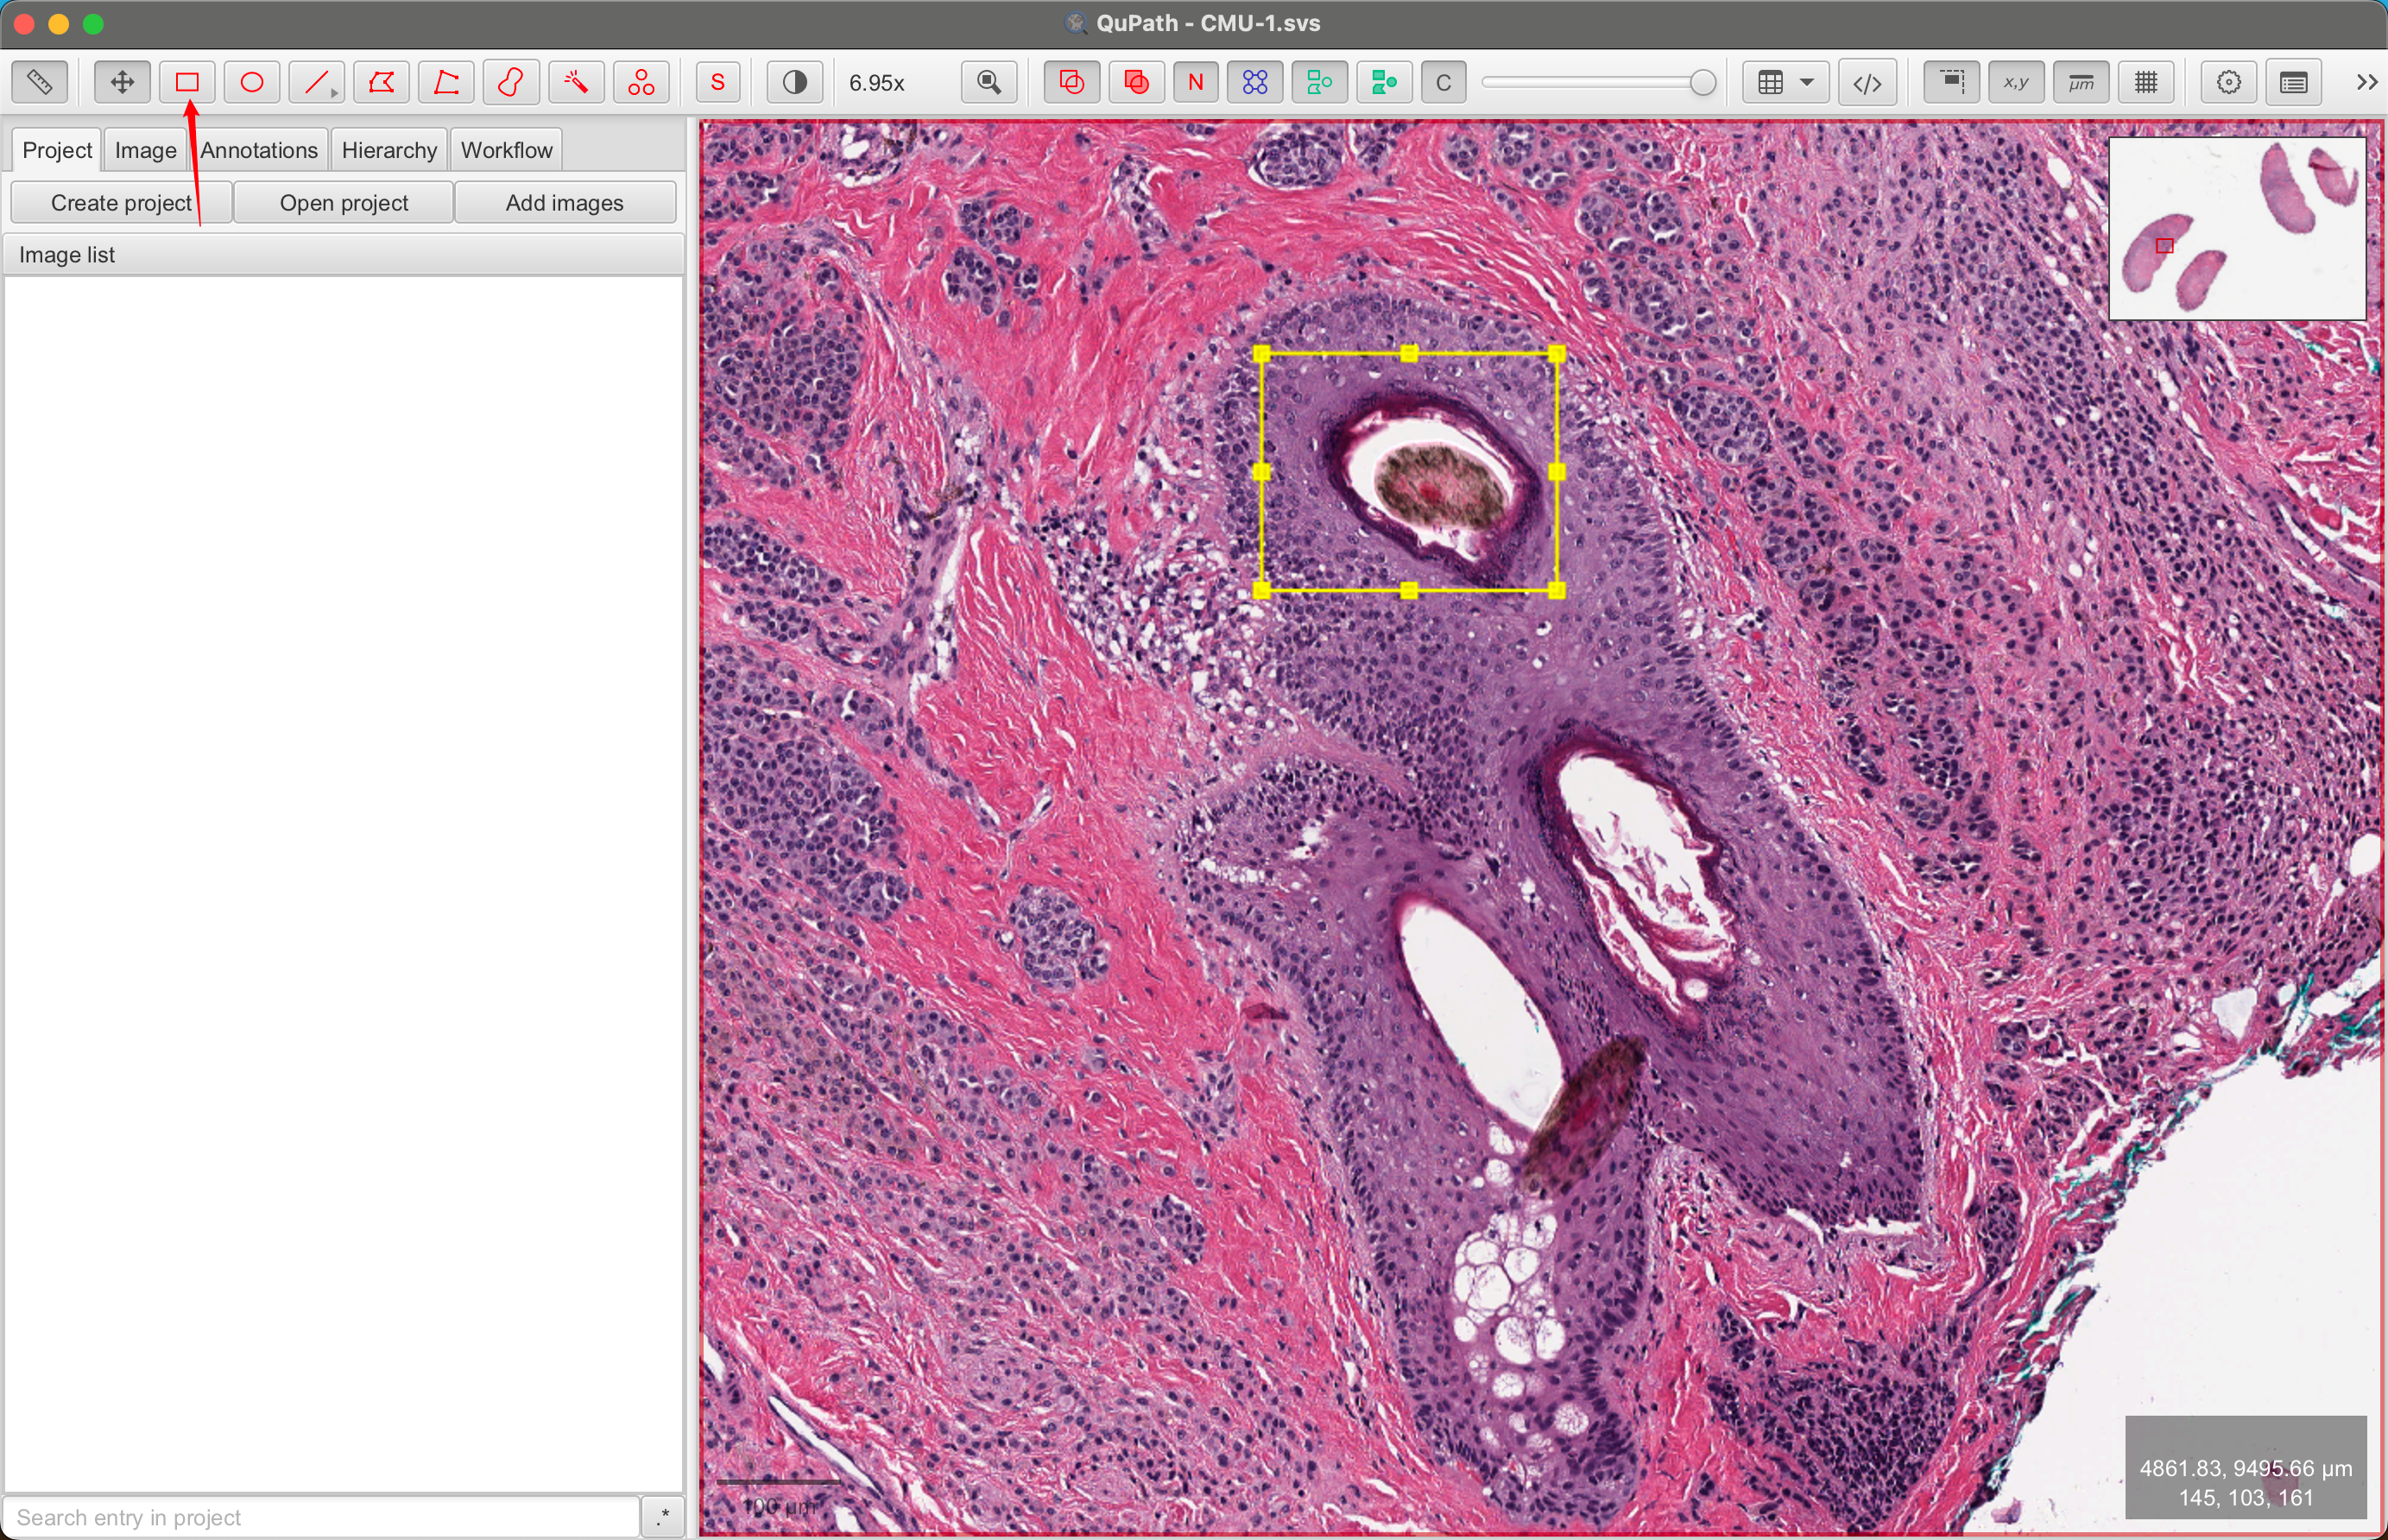

2-4:绘制注释

通过在图像顶部绘制一个矩形来创建您的第一个注释对象。

首先,点击矩形工具 …/…/images/RECTANGLE_TOOL.png 来选择它,然后点击并拖动图像中的一个区域。释放鼠标按钮时,矩形应该仍然显示在图像顶部。

现在尝试使用椭圆 、多边形 和画笔工具 在图像的不同区域绘制几个不同形状的注释。

QuPath的大多数绘图工具工作方式类似(即选择工具,点击图像,拖动鼠标),但请注意多边形工具还允许您避免拖动,而是点击多边形的每个顶点位置。双击以设置最后一个点。

2-5:识别选择

您应该发现,当您绘制一个注释对象时,它最初是被选中的。在上面的屏幕截图中,选中的(多边形)注释显示为黄色 - 带有小方块手柄表示可以调整的顶点。

通常,您希望在进行某些操作之前确保对象已被选中。如果当前没有选中您想要的对象,请返回到移动工具 ,通过点击工具按钮或按M键,然后双击它以进行选择。